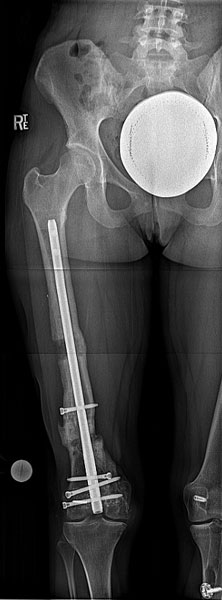

Nicole is a 23 year old woman who was in motor vehicle accident. She sustained an open right femur fracture that required multiple surgeries and left knee ligament damage. She came to the Limb Lengthening and Complex Reconstruction Service 5 years after the injury with problems in the right leg. The right femur was shorter by 1 inch, bowed by 7 degrees, and externally rotated by 10 degrees. She also had pain from the screws around her knee. The xray shows the shortening of the right femur and the varus deformity as well as the screws. Another xray was taken showing her standing on a block to even-out her leg lengths. The difference in the knee heights is evident.